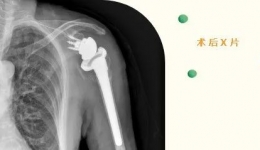

• 【龙中医技术】成都市龙泉驿区中医医院成功开展全区首例反式肩关节置换术!

【龙中医技术】成都市龙泉驿区中医医院成功开展全区首例反式肩关节置换术!

2022年6月,82岁的刁奶奶,因“摔伤致左肩部疼痛伴活动受限2+小时”入住我院骨伤科。入院后,骨伤科许锦涛主治医师通过详细的查体及相关辅助检查,诊断刁奶奶为“1.骨质疏松伴左肱骨近端粉碎性骨折2.左肩关节脱位”。如何让刁奶奶快速恢复左肩关节...

发布时间:2022-07-25|来自:院办